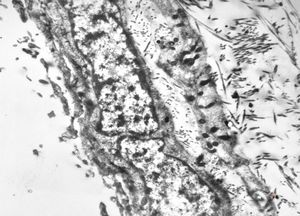

rabbit spinal cord trauma

rabbit spinal cord trauma